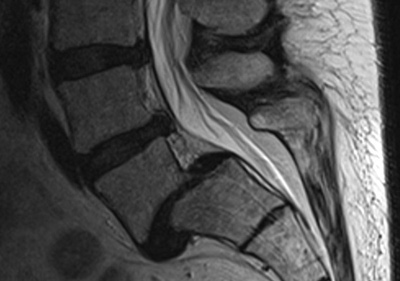

MRT einer Spondylolisthese (Wirbelgleiten) Seitliche MRT-Aufnahme einer Spondylolisthesis der Lendenwirbelsäule. Deutlich sichtbar ist die Stufenbildung zwischen den Wirbeln. © Gelenk-Klinik

Die Diagnosestellung beginnt mit der Erfragung von Krankengeschichte (Anamnese) und Risikofaktoren. Wichtig sind vor allem Vorerkrankungen, Verletzungen und das familiäre Auftreten von Wirbelsäulenerkrankungen. In der klinischen Untersuchung inspiziert der Rückenspezialist den Rücken von außen und achtet dabei auf eine mögliche Stufenbildung der Wirbelsäule. Wichtig sind zudem die allgemeine Körperhaltung und der Stand des Beckens. Ein Schiefstand des Beckens kann auf Probleme in der Wirbelsäule hindeuten.

Weiterhin wichtig für die Diagnose und anschließende Behandlung sind bildgebende Verfahren. Das Röntgenbild zeigt Verschiebungen einzelner Wirbelkörper gegeneinander. Ein MRT oder CT kann zudem die Situation der Weichteile darstellen und zeigt, an welchen Stellen bereits eine Kompression der Nerven stattgefunden hat.